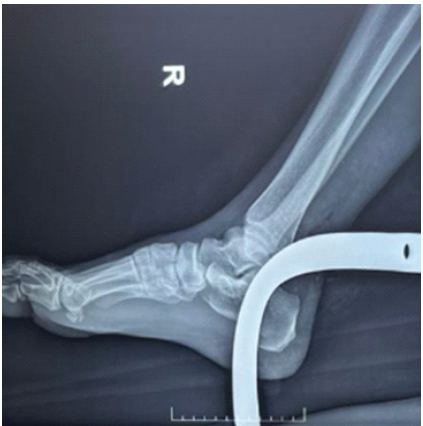

After ensuring intravenous access and adequate analgesia, the patient party was counseled and prognosticated. He was administered tetanus prophylaxis and intravenous antibiotics. Now, attention was given to the wounds. All wounds were first washed with copious amount of normal saline. The visible ends of the two large metallic objects passing through the knee and ankle joints were also gently cleaned of all visible darts with saline and antiseptic solutions. Any fracture of the adjoining bones is quickly ruled out by doing X-ray examinations. Vascular Doppler study of the affected limb showed good biphasic flow in the dorsalis pedis and posterior tibial arteries. Angiogram was not advised by the vascular surgeon. Routine blood investigations, including blood grouping and cross-matching were sent as emergent, and the patient was planned for emergency surgery (Figs. 4 and 5).

Figure 4: X-ray of the knee joint with the metal rotavator blade in situ.

Figure 5: X-ray of the ankle joint showing the rotavator blade in situ.